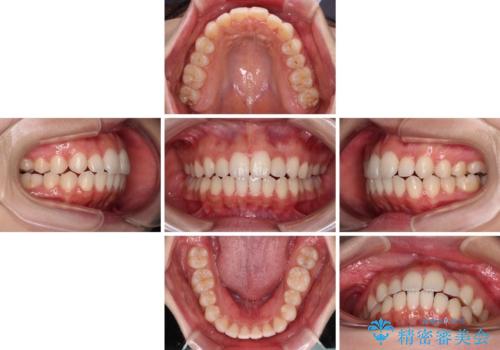

【モニター】前歯のクロスバイトをインビザラインで治療

- 前歯のデコボコとクロスバイトを気にして来院された患者様です。

上顎側切歯(上の真ん中から2番目の歯)が舌側転位している場合、インビザラインでは仕上げきれないことが多く、更には無理して動かそうとすると歯髄壊死を起こすリスクが高いと言われています。

今回は、ワイヤー装置を併用することなく、インビザライン単体で矯正治療を行うこととしました。

インビザライン特有の、奥歯の咬み合わせの問題もなく、しっかりと歯列を改善することができました。

舌側転位している上顎側切歯(内側に引っ込んでいる真ん中から2番目の歯)は、インビザラインが最も移動を苦手とする歯であり、これ以上の改善を望まれる場合にはワイヤー矯正、あるいはワイヤー矯正の併用をお勧めいたします。